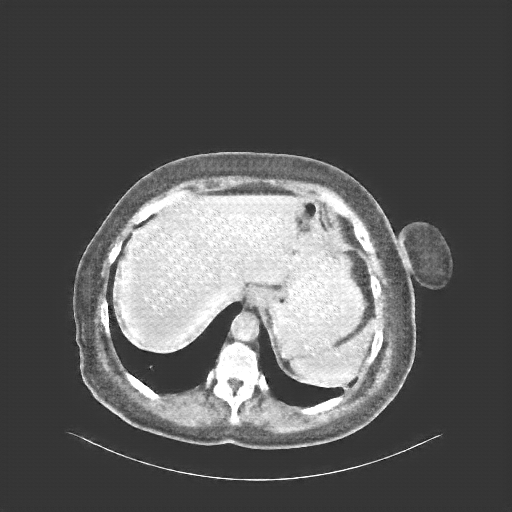

Original NATIVE CT scan (input)

Full window (WL 1023.5, WW 4095 β†’ Low βˆ’1024, High +3071)

Actual HU range: [-160.0, 240.0]

Mediastinum window (WL 40, WW 400 β†’ Low βˆ’160, High +240)